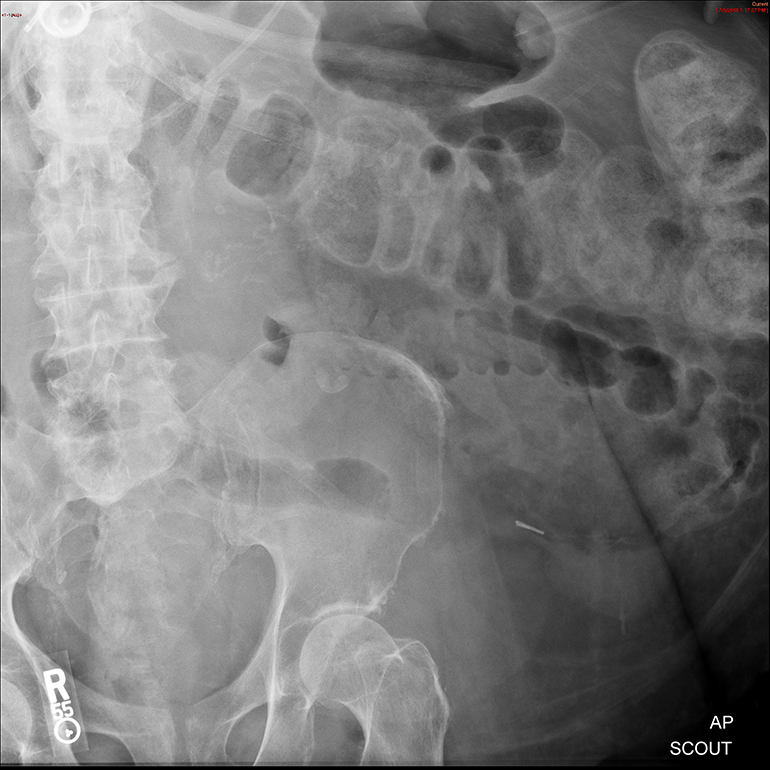

- The technologist will obtain a scout image. Assess the image for any possible contraindications such as pneumoperitoneum, evidence of ileus or obstruction, or residual contrast material

(key image 1).